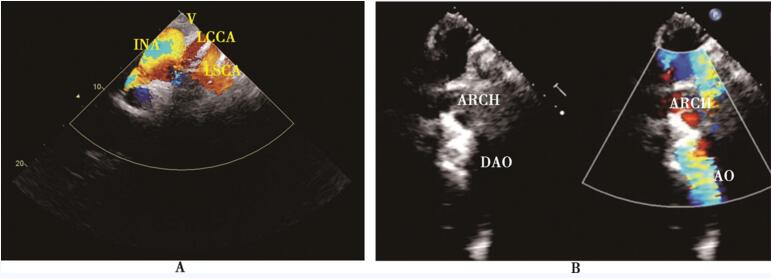

超声心动图可见左心房增大、左心室增大、左心室壁增厚;主动脉弓、主动脉降部异常,头臂干、左颈总动脉、左锁骨下动脉流速增快 (图33-2A),左锁骨下动脉远端的主动脉血流中断(图33-2B),故高度怀疑本病。但超声心动图对本病的诊断存在一定局限性,如由于肺影、胸骨遮挡而不能清晰显示主动脉弓、主动脉降部,或仅显示主动脉弓部而降主动脉下段显示欠佳。

图33-2 超声心动图 A:彩色多普勒超声心动图示头臂干、左颈总及左锁骨下动脉高速花彩血流信号;B:二维、彩色多普勒超声心动图示主动脉弓及降主动脉回声中断。INA:无名动脉;LCCA:左颈总动脉;LSCA:左锁骨下动脉;ARCH:主动脉弓;DAO:降主动脉